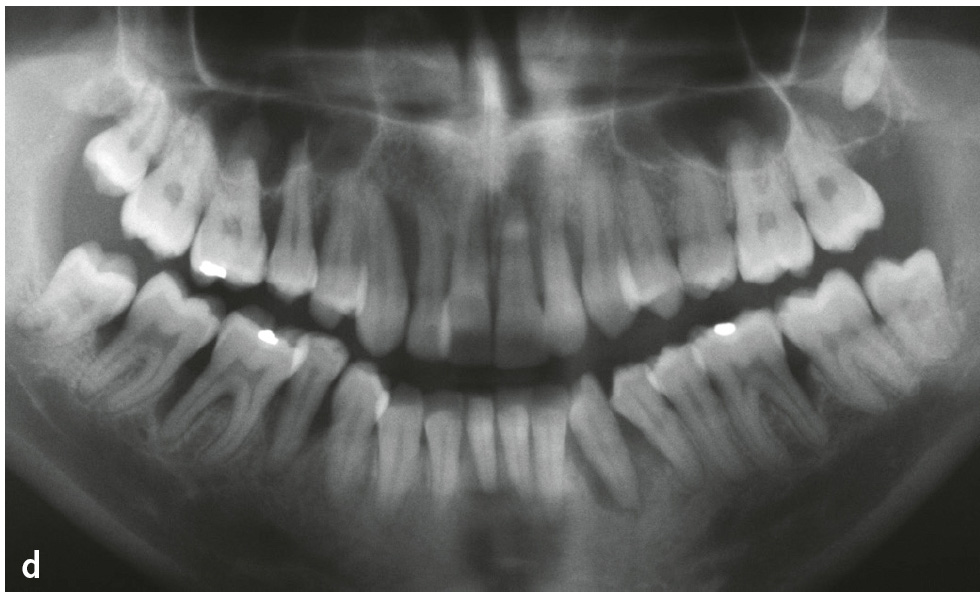

Abb. 1a bis d Parodontitis: a) Mann im Alter von 52 Jahren, Parodontitis, generalisiertes Stadium III, Grad C10: klinische Ansicht (Zahnfehlstellungen im Ober- und Unterkieferfrontzahnbereich, 31 Zahnstein); b) Röntgenstatus zu Abb. 1a: generalisierter überwiegend horizontaler Knochenabbau unterschiedlichen Ausmaßes (bis ins koronale Wurzeldrittel: 15–13, 23, 37–33, 43–47 [bis 33 % der Wurzellänge]; mittlere Wurzeldrittel: 17, 16, 12–22, 24–27, 32–42 [> 33 % der Wurzellänge]; auch am gleichen Zahn (z. B. 36); c) Frau im Alter von 24 Jahren: Parodontitis, generalisiert Stadium III, Grad C10; d) Panoramaschichtaufnahme zu Abb. 1c: Während sich an den Seitenzähnen des 2. Quadranten praktisch kein Knochenabbau findet, weisen andere Zähne Knochenabbau bis ins apikale Wurzeldrittel auf (z. B. 13, 33).